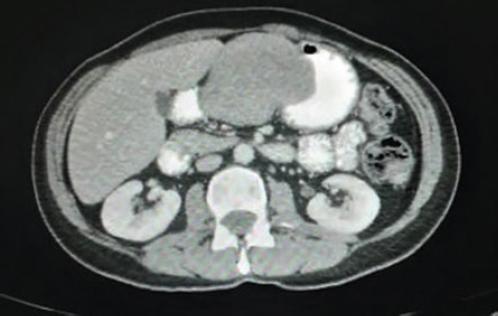

Mujer de 53 años con antecedente de hipertrigliceridemia en tratamiento con fibratos. Es referida por historia de 3 años de evolución de pérdida de peso y saciedad temprana, progresivamente se agrega plenitud posprandial y masa palpable en el epigastrio, motivo por el que se realiza una tomografía contrastada toracoabdominal que reporta una lesión homogénea de contorno bien delimitado en la pared del cuerpo gástrico, de 7.5 × 5.7 × 5.8 cm (Fig. 1). Se realiza endoscopia superior y se encuentra una lesión subepitelial umbilicada en la curvatura menor a nivel de la unión del cuerpo con el antro gástrico (Fig. 2); se complementa con sonografía endoscópica (Fig. 3), con hallazgo de una lesión sólida hipoecoica en la pared gástrica que se origina en la capa muscular externa, bien circunscrita, con medidas de 4.9 × 4.3 cm. Se toman biopsias por aspiración con aguja fina, con reporte de citología transprocedimiento de tumor fusocelular. Se decide el manejo quirúrgico por sospecha de tumor del estroma gastrointestinal (GIST, gastrointestinal stromal tumor) y por la sintomatología en ese momento (Fig. 4). Durante la intervención se encuentra una tumoración firme en la curvatura menor que se extiende al antro gástrico. Se realizan gastrectomía distal (Fig. 5) y anastomosis gastroyeyunal en Y de Roux, sin complicaciones durante el procedimiento.

Figura 1 Tomografía simple toracoabdominal que muestra una tumoración a expensas de la pared del cuerpo gástrico.